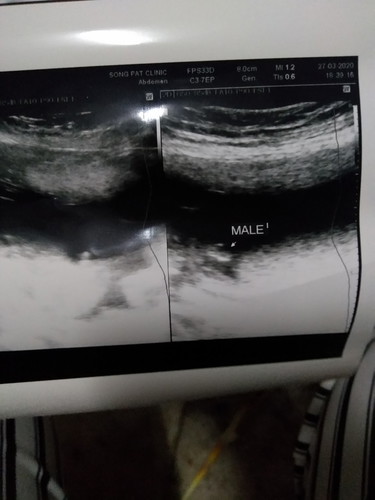

หมอบอกว่าผู้ชาย...แต่บอกว่ายังไม่แน่อีก4Wจะดูให้อีกที แม่ๆว่าผู้ชายจริงไหมค่ะ

น่าจะชายแหละค่ะ